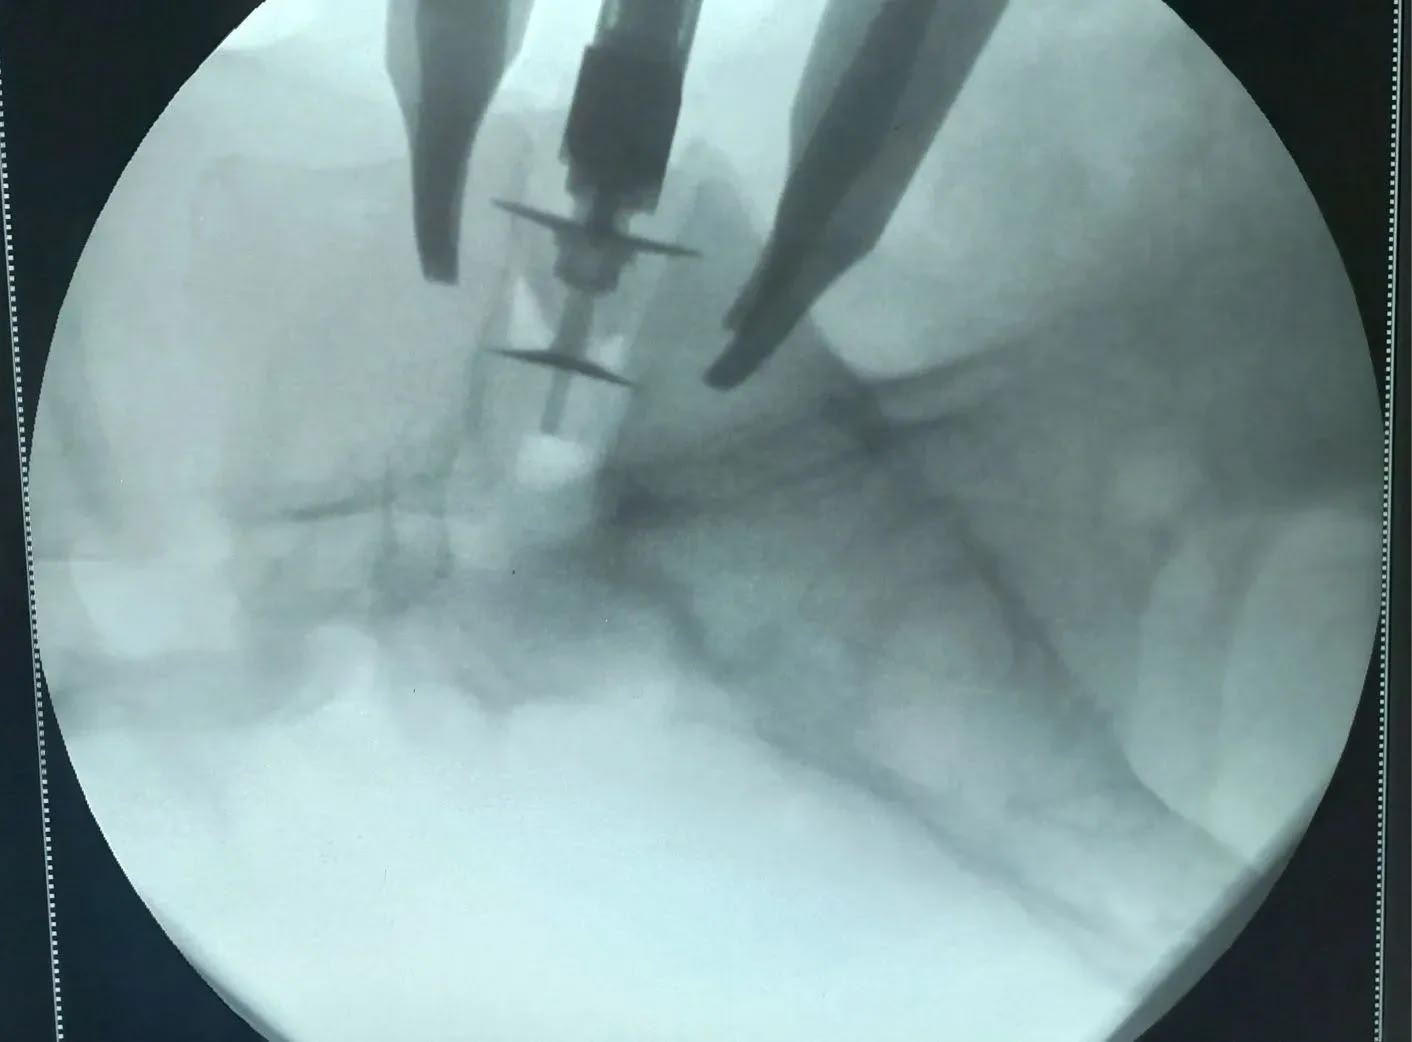

В региональном нейрохирургическом центре (на базе областной больницы № 1) начали выполнять операции по методике ALIF (артродез позвоночника с передним внебрюшинным доступом).

🔹 Хирург работает на передней части позвоночника: удаляет повреждённый диск и ставит имплантаты, которые фиксируют позвонки и освобождают нервные корешки.

* два вмешательства на уровне L5‑S1 (между поясничным позвонком и крестцом);

* одно — на уровне L3‑L4 (между третьим и четвёртым поясничными позвонками).